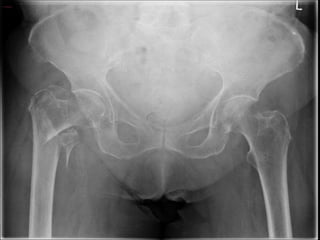

DIAGNOSTIC IMAGING

• X-ray is the standard diagnostic tool.

• When a hip fracture is suspected but not apparent on standard x-

rays, a technetium bone scan or a MRI scan should be obtained.

• MRI has been shown to be at least as accurate as bone scanning in

identification of occult fractures of the hip, and it will reveal a

fracture within 24 hours of injury.

DIAGNOSTIC IMAGING • X-rayis the standard diagnostic tool. • When a hip fracture is suspected but not apparent on standard x- rays, a technetium bone scan or a MRI scan should be obtained. • MRI has been shown to be at least as accurate as bone scanning in identification of occult fractures of the hip, and it will reveal a fracture within 24 hours of injury.